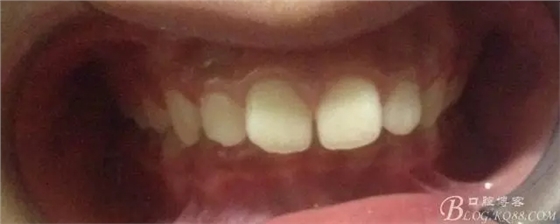

努力沒有白費(fèi),中線基本對齊!

一晃快兩年了,我覺得關(guān)節(jié)重建及咬合穩(wěn)定,再加上患者的急迫愿望,我們拆除了矯正器。

尖牙關(guān)系中性,磨牙關(guān)系中性,咬合鎖結(jié)良好!

15歲了,1米78的個頭,陽光帥氣的他,側(cè)貌堪比天安門國旗手的面型?。釘懒耍?p style="text-align: left;">640.webp (24).jpg